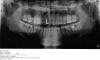

Nicholas Опубликовано 23 мая, 2013 Поделиться Опубликовано 23 мая, 2013 Ну вот наконец то нашел время сделать снимок, к сожалению на диск не скинули распечатали на простой бумаге, отсканировал как смог. Сверху зуб отломан почти также как и снизу но этого почти не видно на снимке. Подскажите с чего начать лечение?И насчет прикуса насколько я знаю сейчас в любом возрасте можно брекеты поставить и выпрямить или нет? Ссылка на комментарий

red_butler Опубликовано 24 мая, 2013 Поделиться Опубликовано 24 мая, 2013 На снимке видно следствие хронического воспалительного процесса в области зубов мудрости на нижней челюсти, плюс слева отсутствует мудрый зуб сверху Ссылка на комментарий